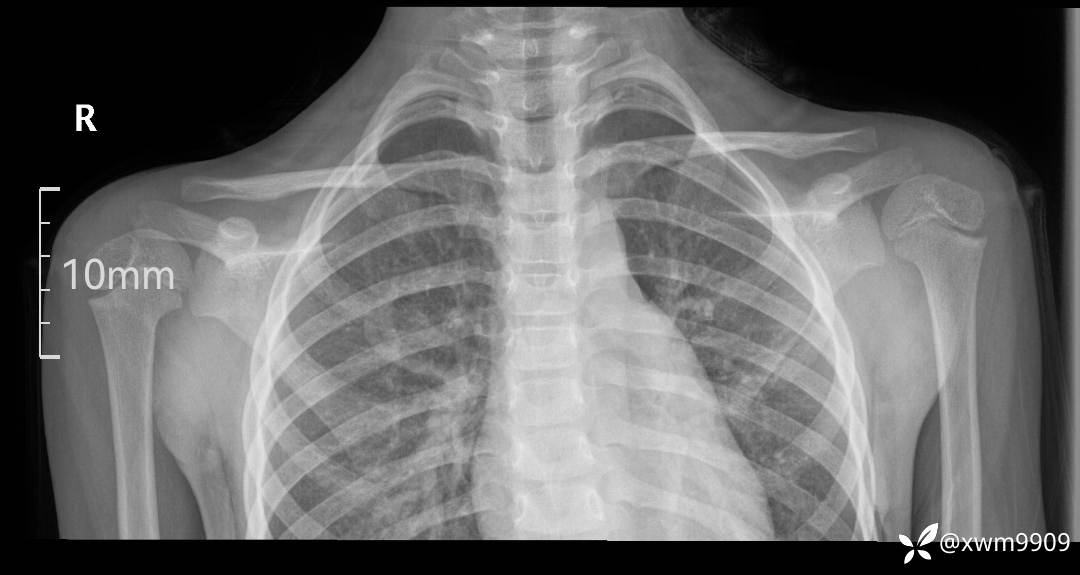

2024-03-19,门诊“摔伤右锁骨肿胀疼痛6小时。拟“锁骨骨折”要求摄:右肩关节正侧位,右锁骨轴位检查。

DR: